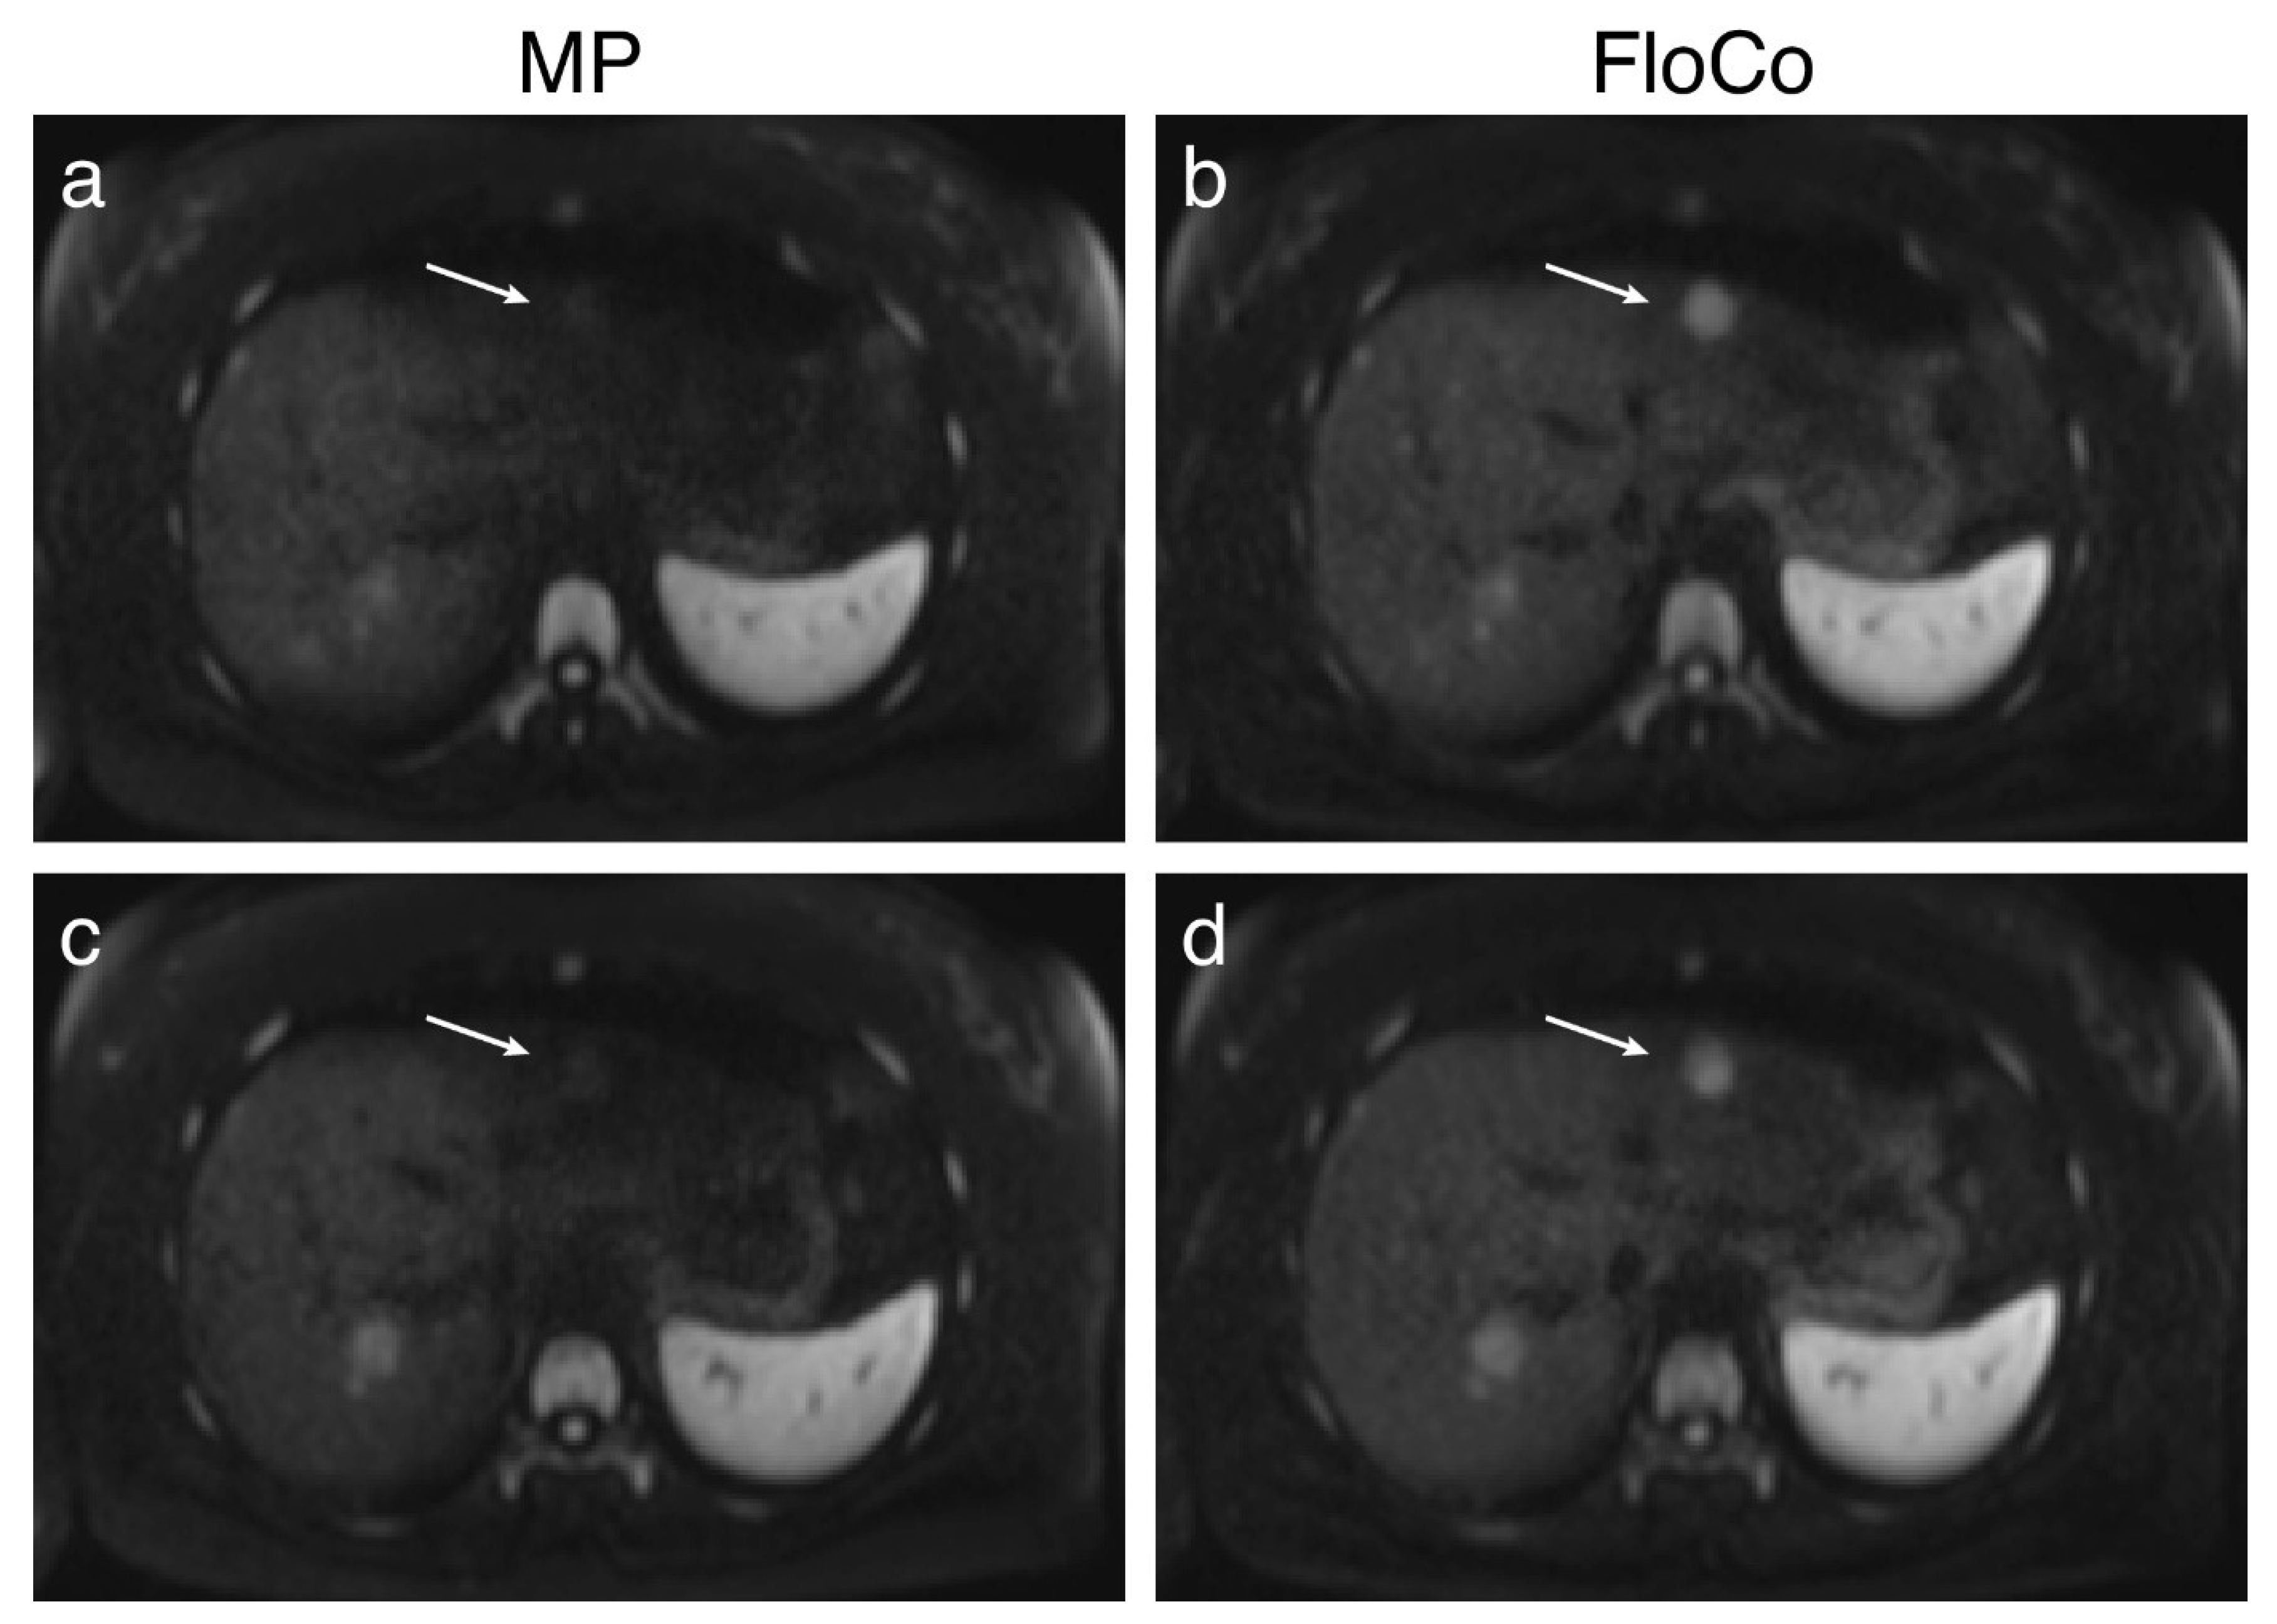

3.2. Representative Images